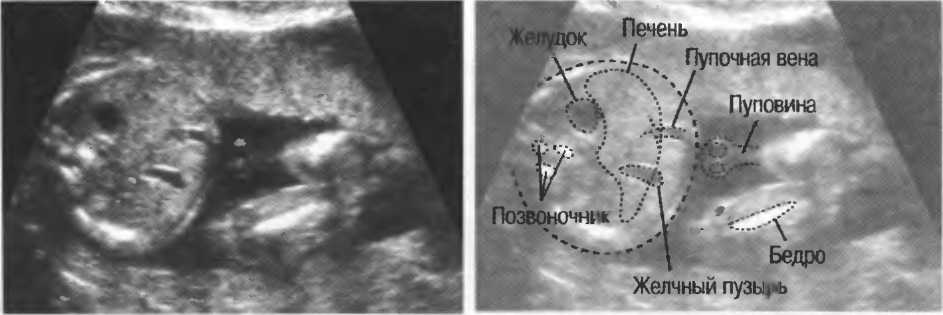

Рис.5. Два поперечных среза плода, демонстрирующих тень от позвоночника плода. Аналогичная тень от ребер может частично закрывать почки или печень. Изменяя угол наклона датчика, можно изменить положение тени таким образом, чтобы подлежащие ткани были видны отчетливо.